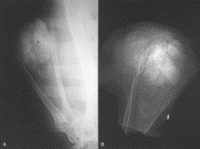

• Radiology